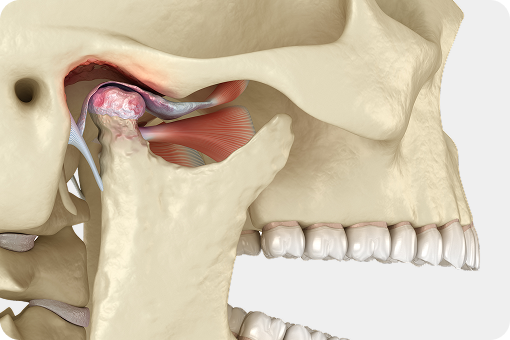

통합치의학과 전문의 대표원장이 시작부터 끝까지 맞춤케어 해드리겠습니다.

어려운 케이스일수록

자신 있습니다.

당뇨 · 고혈압 등 전신질환 수술을 받으신 분부터 재수술이 필요하신 분들까지.

원칙대로 진행한다면, 문제가 생길 수 없습니다.